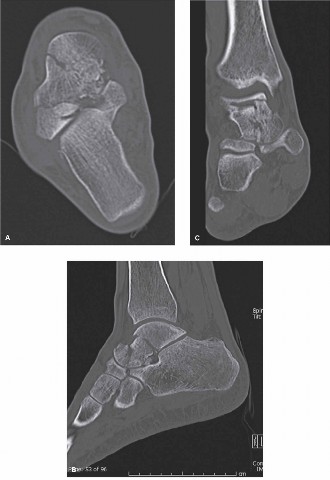

2. Computed Tomography (CT) Scan: Mandatory for all displaced talar neck fractures. CT provides detailed information regarding:

* Fracture pattern, comminution, and articular involvement (ankle, subtalar, talonavicular joints).

* Degree and direction of displacement, impaction, and rotation.

* Presence of incarcerated fragments within joint spaces.

* Associated subtle fractures or dislocations not evident on plain radiographs.

* Planning screw trajectories and identifying potential fixation points.